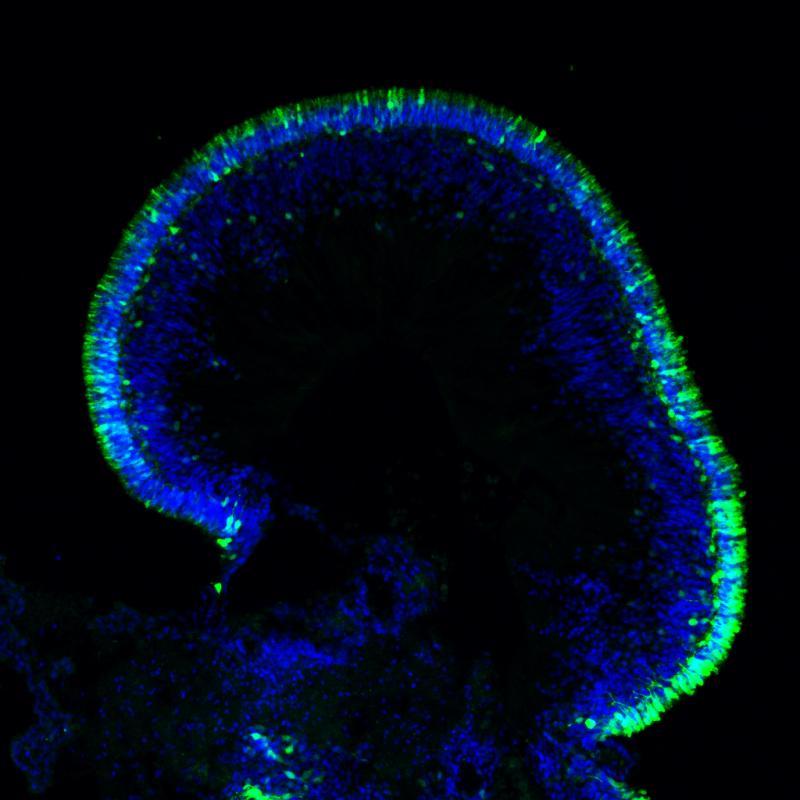

Recent Retina Organoid Review Articles

Retina Organoid Differentiation Protocols

Retina Organoid Characterization Methods